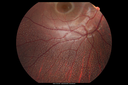

12 year old female She went last December for her regular checkup and spots were noted on the retina in the periphery. Her vision is fine and there is no family history of retinal disease. She has difficulty seeing at night and finding her way in a dark theater. VA OD: Dcc20/20-1 NccJ1+ VA OS: Dcc20/20 NccJ1+

Fundus Albipunctatusvista 962 veces12 year old female with normal vision. She has 4 siblings all of whom have either white spots or spots on IR. Genetic testing by parents was deferred.00000